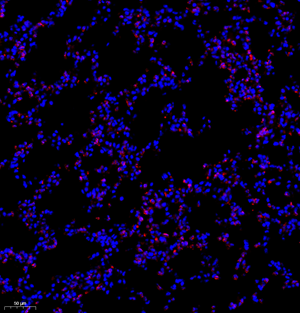

| IF analysis of MPO (GB11224). Sample: Mouse lung+lps (Paraffin), 4% PFA (G1101) 12-24h. Antigen retrieval: TE buffer (pH 9.0) (G1203),98°C,20min. Blocking buffer: 3% BSA in PBS (GC305010), RT, 30min. Primary antibody: 1: 1200, 4°C overnight. Secondary antibody: Cy3 conjugated Goat Anti-Rabbit IgG (H+L) (GB21303), 1: 300 RT, 1h. |